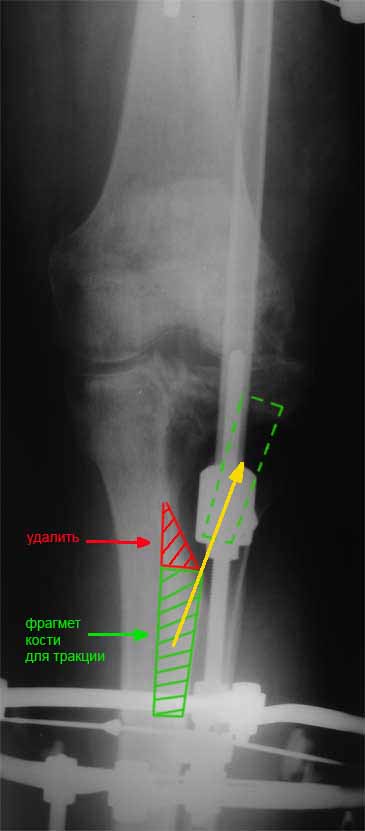

Я бы сделал пластику мягких тканей (торакодорзальный лоскут совместно с микрохирургами или пластику латеральной головкой икроножной мышцы) и выполнил бы краевой отщеп большеберцовой кости для его дистракции аппаратом в проксимальном направлении (рис. 1 – пример применения отщепа (авторство не мое), рис. 2 – схема предлагаемого варианта замещения дефекта кости).

Малоберцовую кость я бы пока не трогал. Она сослужит хорошую службу при начале нагрузки на ногу - будет служить дополнительным стабилизирующим и элементом.

>и выполнил бы краевой отщеп большеберцовой кости для его дистракции аппаратом в проксимальном направлении

- это можно, но... про м/т я уже говорил